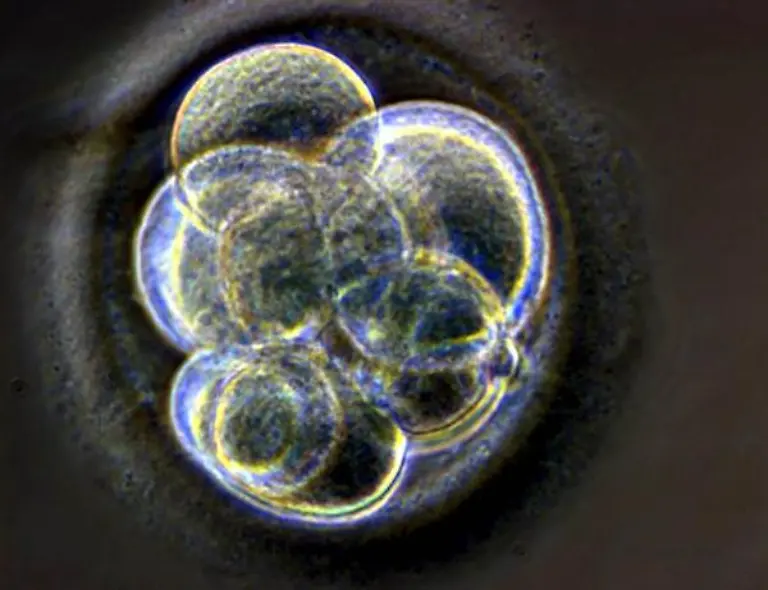

Wegweisend in der Heilung von Krankheiten oder ein unmoralischer Eingriff in den Lauf der Natur? Klonen ist so umstritten wie kaum ein anderes Thema. 1996 machte Dolly von sich reden. Längst haben sich die Klone von einst auf natürlichem Wege fortgepflanzt.